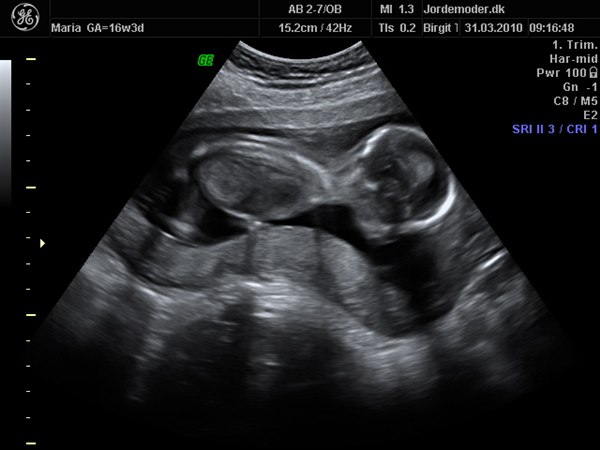

det blir en dreng endnu engang :)

var til skanning idag og ingen tvivl om hvad det bliver

er nu i 16+3

alt var i den skønneste orden og perfekt